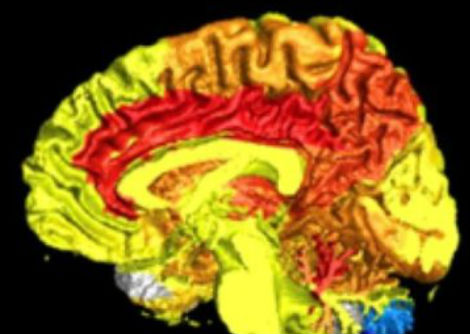

عرّض الباحثون الفئران للكحول أو دخان التبغ أو كليهما مرتين يوميًا لمدة 28 يومًا. قارن الباحثون أدمغة هذه الفئران بفئران لم تتلق أي عقار من العقاقير. وجد الباحثون أن تناول الكحول والتدخين معًا قد زاد من مستوى الأكسجين التفاعلي في منطقة في الدماغ تعرف بقرن آمون (Hippocampus) مقارنة بالحيوانات التي لم تتعرّض للعقاقير أو الفئران التي تعرضّت لدخان التبغ وحده. أدى الجمع بين الكحول والتدخين إلى زيادة مستويات السيتوكينات المضادة للالتهابات في جميع مناطق المخ التي شملتها الدراسة.

أظهرت الفئران التي تلقّت كلا العقارين مستويات منخفضة من عامل التغذية العصبية، وهو عامل نمو يساعد الخلايا العصبية الموجودة على البقاء ويحفز نمو خلايا جديدة، في منطقتي النواة المخططية striatum والقشرة الأماميّة frontal cortex.